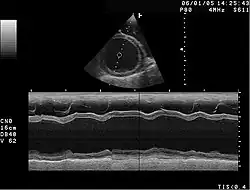

M-Mode-Darstellung der DCM. Der Herzmuskel zeigt eine Kontraktilität von etwa 10 % (normal: >25 %) und ist stark erweitert.

Bei Kleintieren zählen Kardiomyopathien zu den am häufigsten beobachteten Herzerkrankungen. Die Ausprägungen unterscheiden sich je nach Tierart und Rasse erheblich.

Hunde

Bei Hunden ist die dilatative Kardiomyopathie (kurz DKMP oder DCM) die dominierende Form dieser Herzerkrankung. Vor allem die Vertreter größerer Rassen neigen zu diesem Leiden, während Angehörige kleinerer Hunderassen häufiger von Degenerationserscheinungen des Endokards im Klappenbereich betroffen sind. Einen einfachen Anhaltspunkt gibt hier die sogenannte „Ein-Hand-Regel“. Kann der Hund mit einer Hand angehoben werden, hat er wahrscheinlich keine Kardiomyopathie.